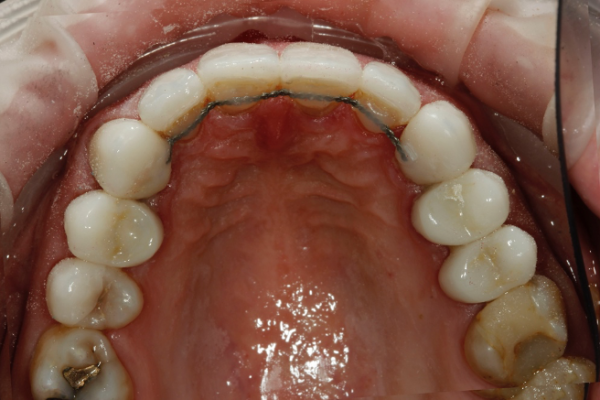

So, prior to a hygiene work up, the patient was then assessed from an orthodontic perspective for short-term pre-restorative orthodontics. This was to improve tooth position (Figures 2 a,b and c) and allow for a less destructive tooth preparation.

The treatment time in fixed orthodontics was 2.5 months. This focused mainly on the maxillary anterior teeth. Dual arch fixed orthodontic appliances were placed. Mainly to allow for use of additional elastics to expedite finishing. Elastics were also used within the upper arch to redistribute space to further minimise invasiveness by reducing the reliance upon IPR (Figure 3).

Post orthodontically, the patient had fixed and removable retainers provided. The patient is educated from the very start that this will be a lifelong commitment for them (Figures 4a and b).

Once the ceramics were fitted in this case, the maxillary upper and lower fixed retainers, which were removed at the stage of preparation, were re-fitted for definitive fixed retention. Thereafter jointly retained with definitive removable Essix retainers (Figures 6 a, b, c and d).